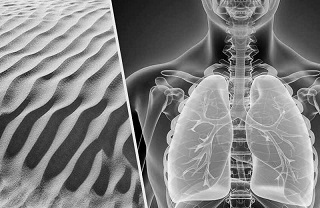

सिलिका कणों के फेफड़ों में पहुंचने पर फेफड़ों में धब्बे पड़ने लगते हैं। खांसी इसका शुरुआती लक्षण है जो सिलिका के निरंतर प्रवेश से बढ़ती जाती है। अंतर्राष्ट्रीय श्रम संगठन ने सिलिकोसिस की पुष्टि के लिए पारंपरिक एक्स-रे, मेडिकल हिस्ट्री और स्टैंडर्ड लंग फंक्शन टेस्ट आवश्यक बताए हैं। दुर्भाग्यवश इन जांचों से भी इसकी पुष्टि तभी संभव हो पाती है जब रोग अंतिम चरण में पहुंच चुका होता है।

सिलिकोसिस के रोगियों में अन्य बीमारियों, जैसे टीबी, फेफड़ों में कैंसर और जीर्ण दमा का जोखिम भी बढ़ जाता है। सिलिकोसिस के लक्षण टीबी के लक्षणों से मिलते-जुलते होने के कारण भी इसकी पहचान आसान नहीं है। टीबी रोगाणुओं की घुसपैठ के कारण सिलिकोटिक नोड्यूल्ज़ की गलत पहचान होने से भी सिलिकोसिस के रोगियों के एक्स-रे की व्याख्या करना मुश्किल हो जाता है।